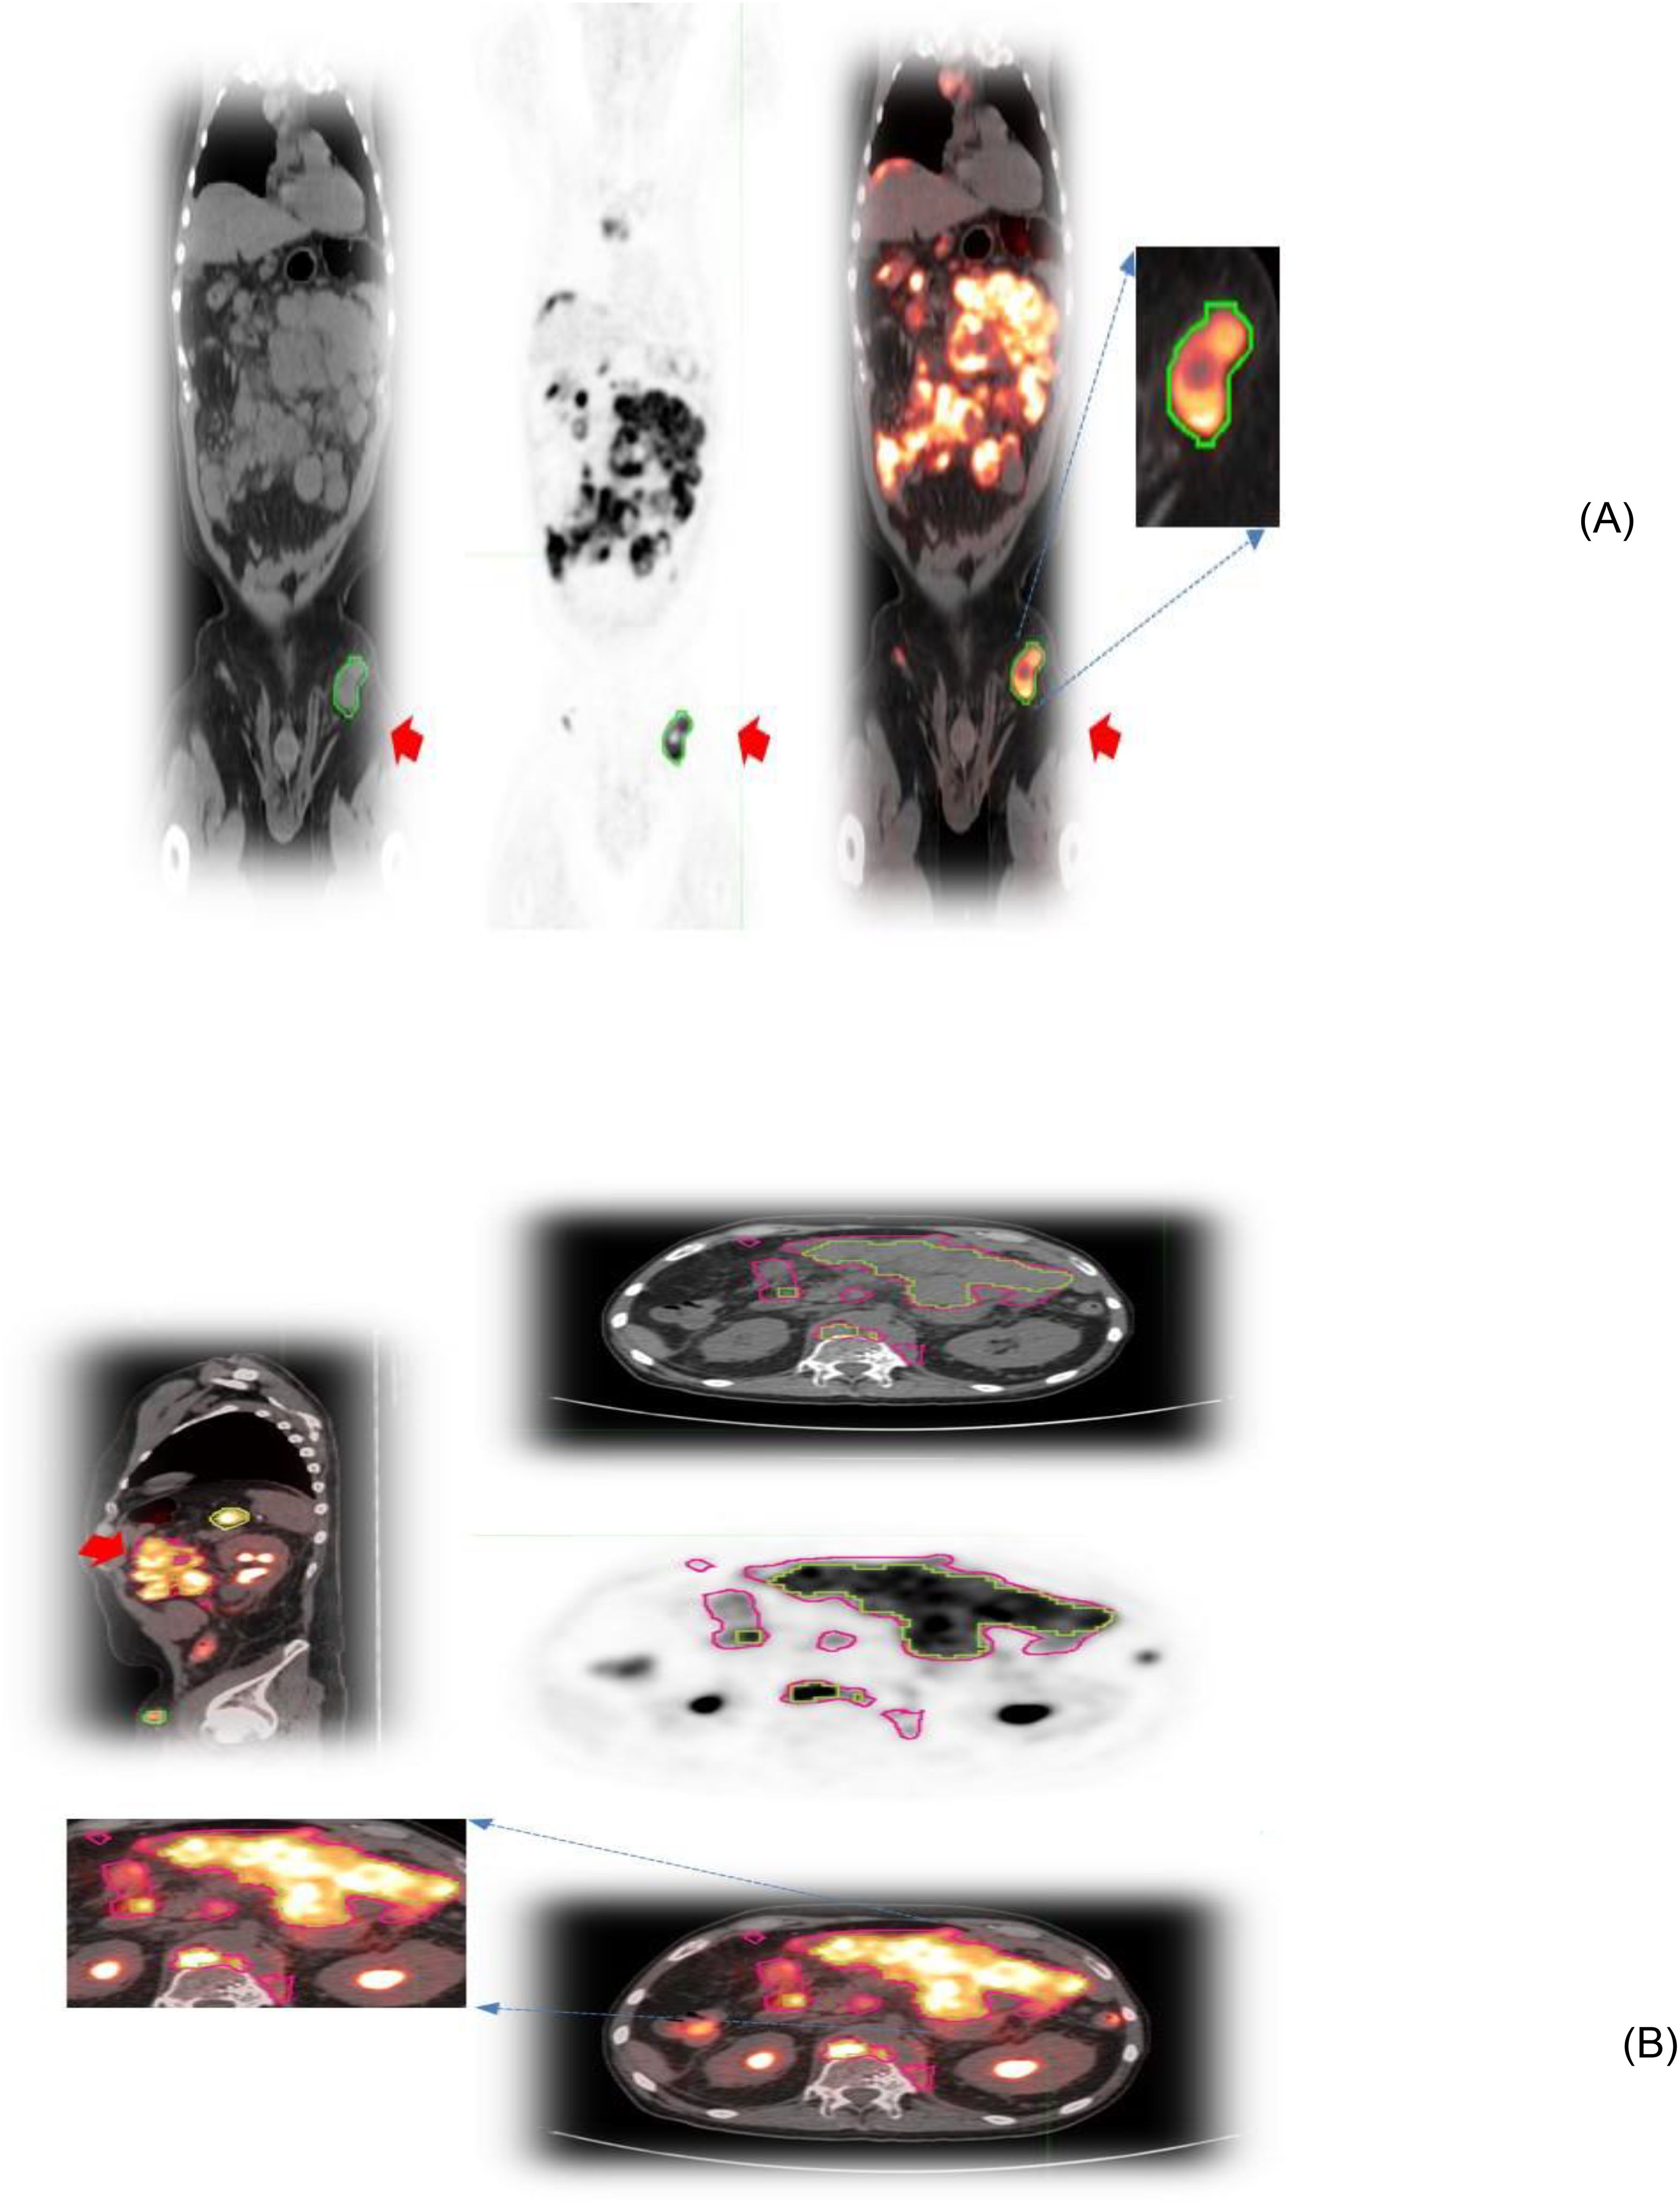

Facilitate learning with our scientific Pet/ct Lymphatic System gallery of hundreds of educational images. accurately representing photography, images, and pictures. perfect for research publications and studies. Browse our premium Pet/ct Lymphatic System gallery featuring professionally curated photographs. Suitable for various applications including web design, social media, personal projects, and digital content creation All Pet/ct Lymphatic System images are available in high resolution with professional-grade quality, optimized for both digital and print applications, and include comprehensive metadata for easy organization and usage. Explore the versatility of our Pet/ct Lymphatic System collection for various creative and professional projects. Multiple resolution options ensure optimal performance across different platforms and applications. Whether for commercial projects or personal use, our Pet/ct Lymphatic System collection delivers consistent excellence. Professional licensing options accommodate both commercial and educational usage requirements. Each image in our Pet/ct Lymphatic System gallery undergoes rigorous quality assessment before inclusion. Time-saving browsing features help users locate ideal Pet/ct Lymphatic System images quickly. Advanced search capabilities make finding the perfect Pet/ct Lymphatic System image effortless and efficient. Comprehensive tagging systems facilitate quick discovery of relevant Pet/ct Lymphatic System content. Instant download capabilities enable immediate access to chosen Pet/ct Lymphatic System images.